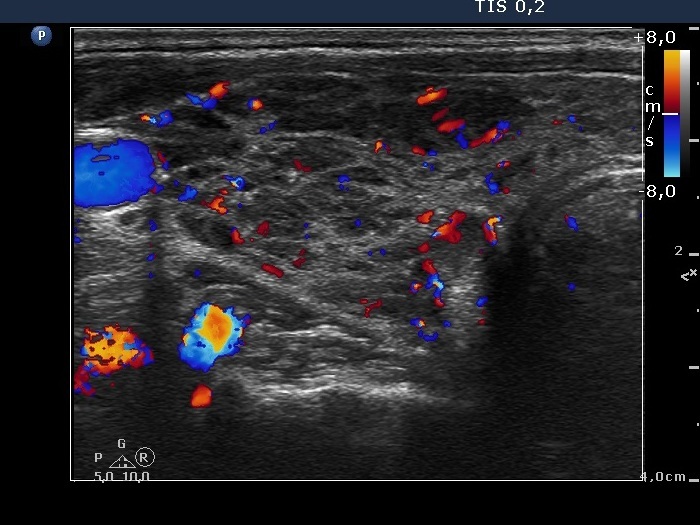

Ultrasonography: The thyroid presented the so-called honey-combing pattern: connective tissue septum divided the hypoechogenic thyroid into smaller areas.

Diagnosis: Hashimoto's thyroiditis.

Comment. It is to be avoided to overrate the relatively larger hypoechogenic areas as nodules.